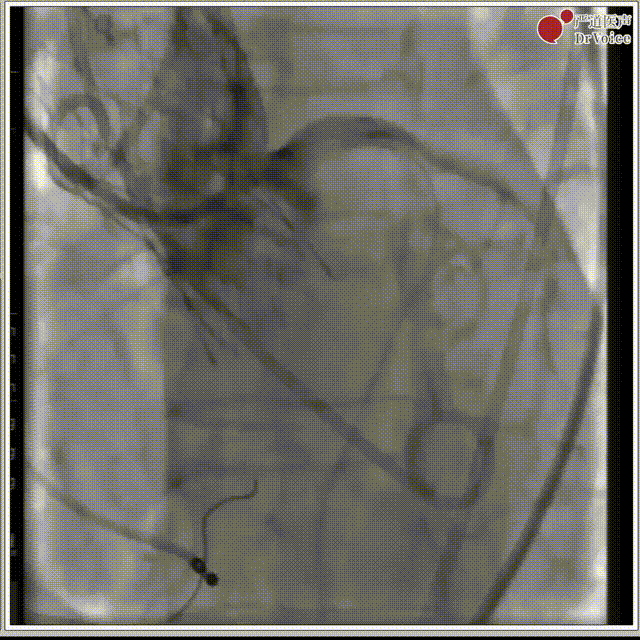

4. 植入23mm Evolut PRO瓣膜,过弓及瓣膜定位。

过弓,植入瓣膜

主动脉根部造影

5. 第一次深度偏深,半回收。

第一次释放

6. 第二次释放,左、右前斜深度及冠脉评估,决定释放瓣膜。

第二次释放

左前斜LCC

最后释放